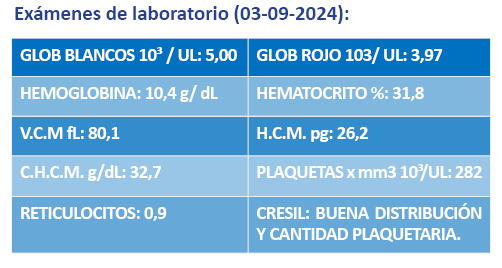

Serie Roja:

anisocitosis +, microcitosis +, hipocromía +. No se evidencian alteraciones en la forma de los glóbulos rojos, Serie blanca: leucocitos en cantidad normal, neutropenia moderada y linfocitos normales.